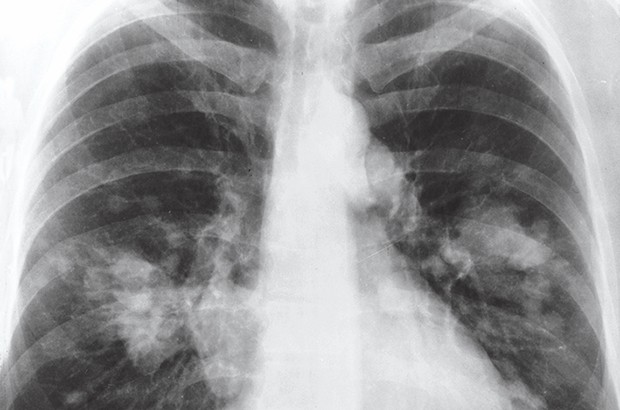

En marge de l'opération "Portes ouvertes sur la sensibilisation contre le tabagisme", organisée par la Cnas de Mostaganem, nous avons appris que 241 patients en 2015 et 302 autres en 2016 sont atteints de cancers de l'appareil respiratoire, orientés vers le service d'oncologie de Mazagran en vue d'une prise en charge en séances de chimiothérapie. Lors de la mini-campagne de sensibilisation au tabagisme, initiée par la Cnas, un pneumologue a tiré la sonnette d'alarme quant aux effets dévastateurs du tabac observés sur le terrain. Le conférencier a souligné que dans un foyer, lorsqu'une personne aura fumé 10 cigarettes, les autres membres de sa famille auront tout de même consumé une cigarette sans la fumer réellement, ce qu'on appelle le tabagisme passif, tout aussi nocif. Se voulant particulièrement persuasif, le médecin insistera sur l'indisponibilité à l'heure actuelle d'un quelconque traitement du cancer des poumons. La chimiothérapie reste inopérante. "Dès lors, le meilleur remède tient en la volonté ferme d'abandonner la cigarette", conclura-t-il en exhortant les gens à ne plus fumer. Au sujet du tabagisme passif, et à l'adresse des parents fumeurs, cette campagne est initiée à la direction de la wilaya par une série de communications animées par des médecins. Des conclusions d'une enquête menée auprès d'un échantillon d'assurés affiliés à la Caisse nationale d'assurance maladie de Mostaganem révèle que 27,6% des assurés interrogés sont des fumeurs, avec une prévalence plus élevée chez les hommes. Selon le même sondage, près du quart de l'échantillon (23,5%) consommait du tabac quotidiennement, alors que 4,1% seulement s'y adonnaient occasionnellement.M. Salah